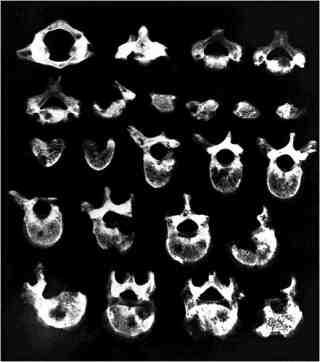

Andreas G. Nerlich and colleagues in Munich tried out the prediction on 905 skeletons from two ancient Egyptian necropolises. With the help of X-rays and CT scans they diagnosed five cancers — right in line with Dr. Waldron’s expectations. And as his statistics predicted, 13 cancers were found among 2,547 remains buried in an ossuary in southern Germany between A.D. 1400 and 1800.